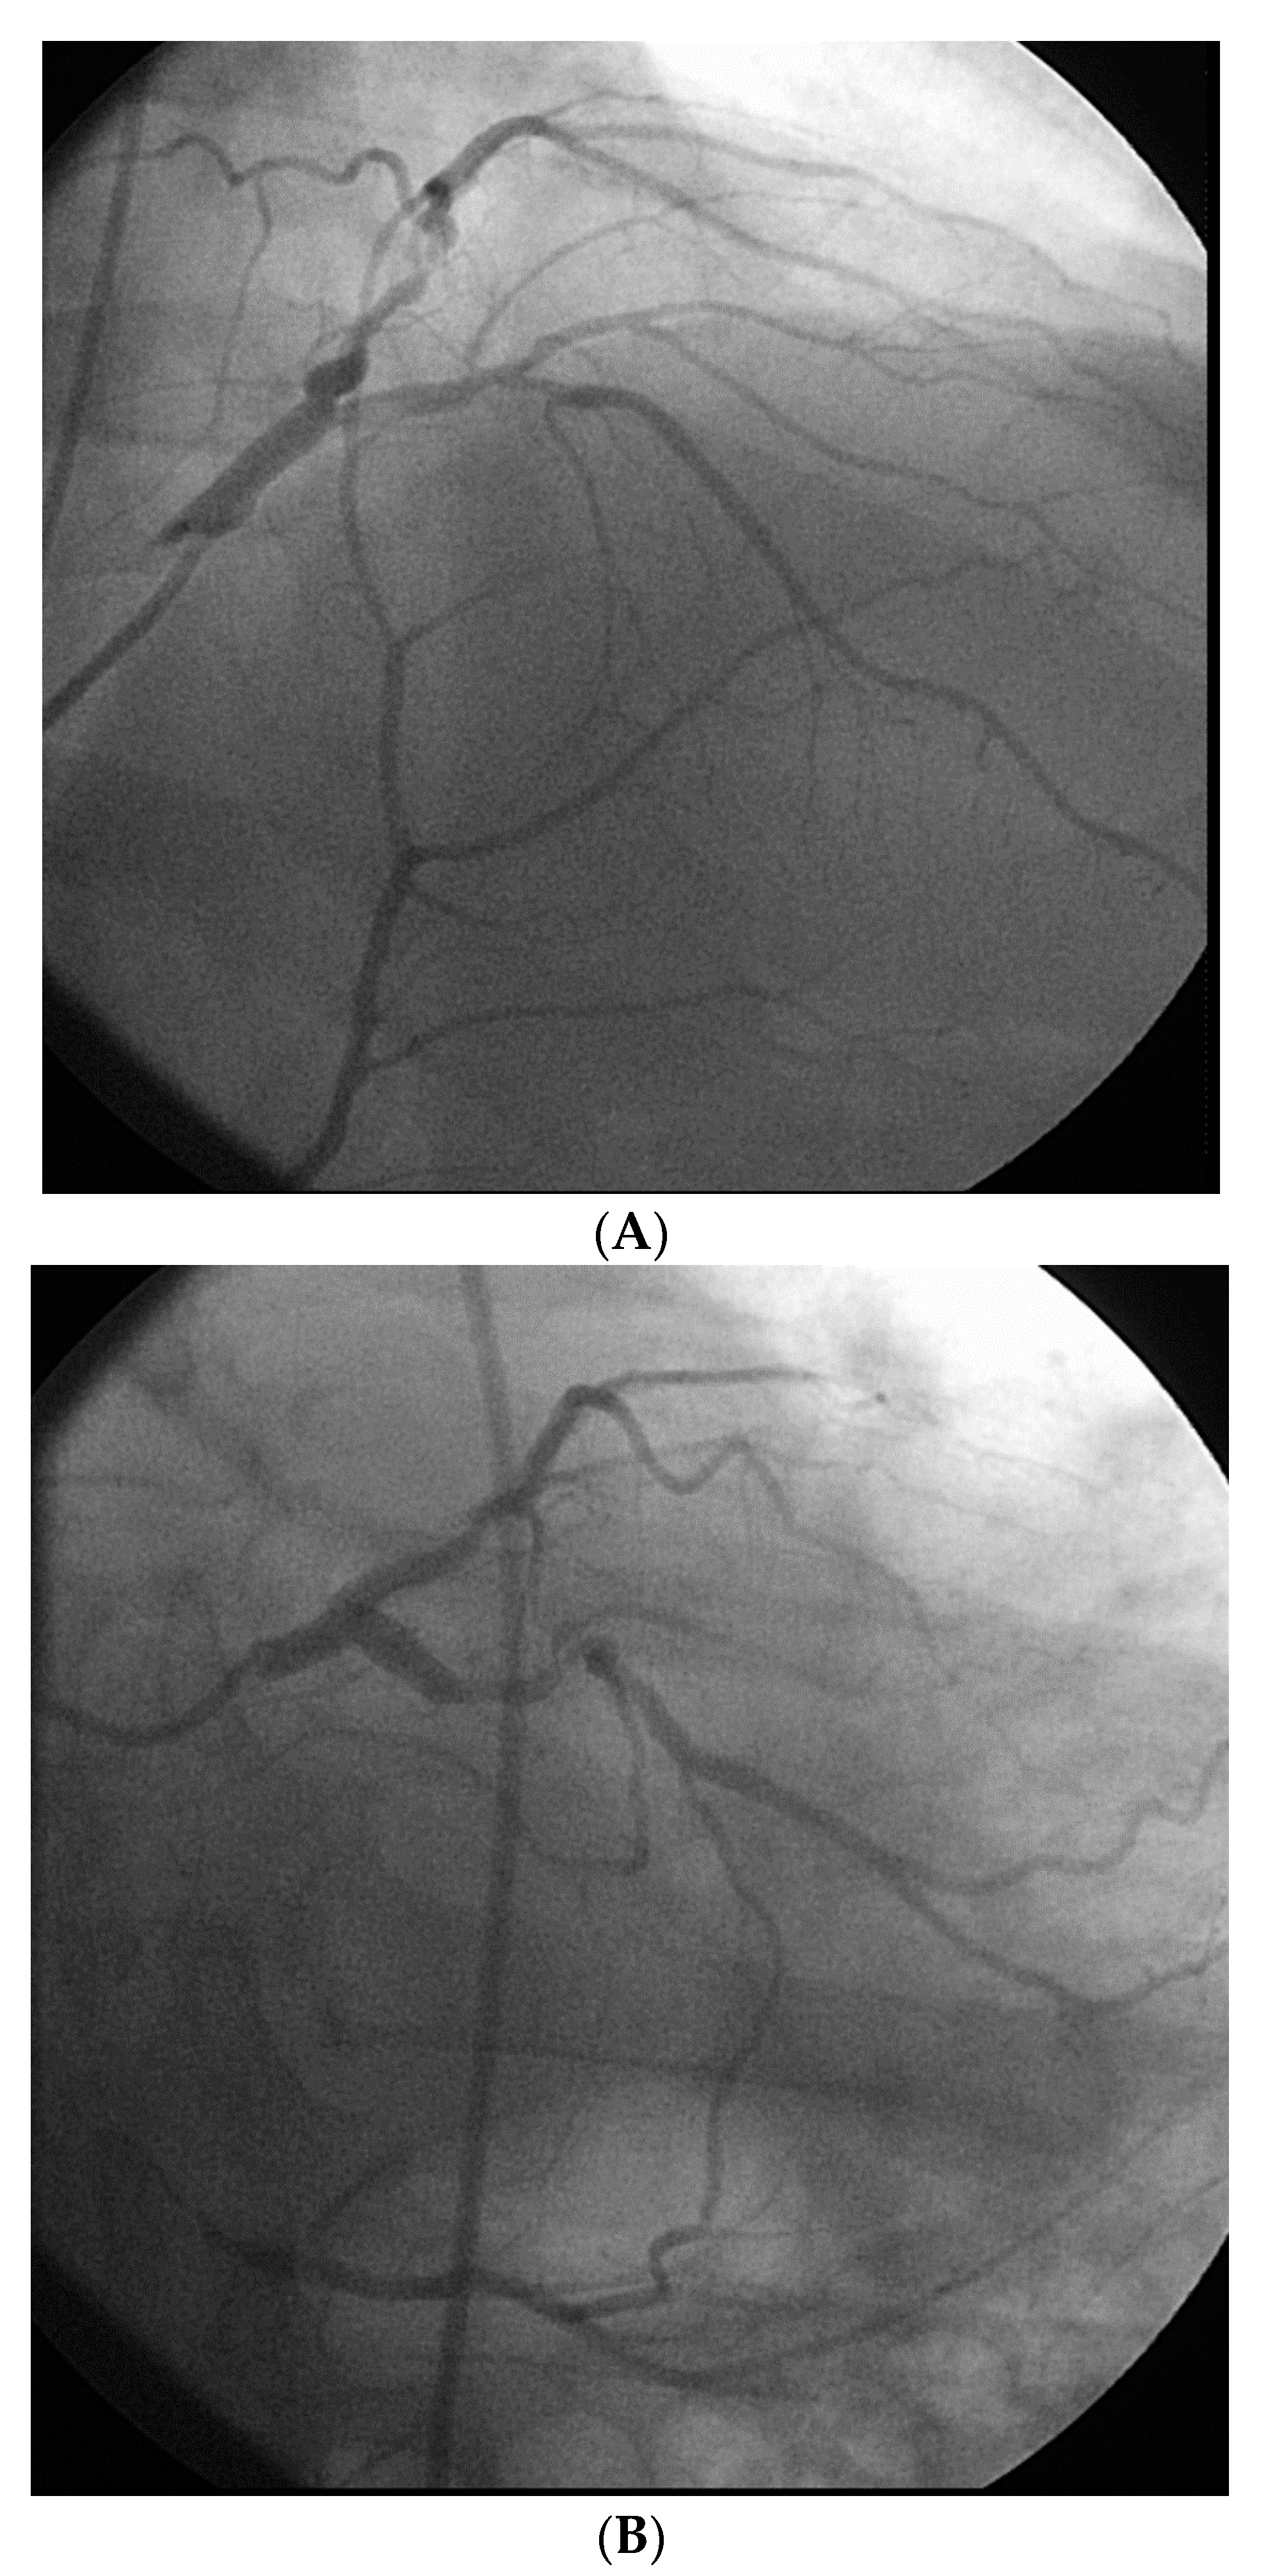

From a pure anatomical standpoint, bifurcation cases with planned kissing stents or kissing balloon angioplasty are not ideal for robotic PCI primarily because the system can only advance one catheter actively. However, bifurcations where provisional side-branch intervention is planned are reasonable choices for robotic PCI. Cases with excessive vessel tortuosity may be successfully performed robotically (Figure 3); however, extreme arterial angulation, or lesions that are severely eccentric or have dissected plaque morphology may require the use of tactile feedback that is not afforded by the robot and are not ideal (Figure 4). Although the advanced wire techniques required for anterograde wire escalation, dissection re-entry approaches, or retrograde approaches in chronic total occlusion intervention are not applicable robotically, we have used the robot to deliver and perform balloon angioplasty, stenting, and post-dilatation after first successfully manually crossing chronic total occlusions with a guidewire (Figure 5). Although the current generation system allows the operator to make fine adjustments in the guide catheter position, ostial lesions, particularly involving the RCA can be very challenging to perform robotically (Figure 6). Finally, cases that require the use of aspiration, atherectomy, filter wires, or certain imaging catheters (OCT and some IVUS), are not suitable for stand-alone robotic PCI.

Figure 3. Example of a complex lesion involving the LAD in a patient with angina and severe tortuosity (A). Despite the tortuosity, the lesion was successfully wired, ballooned, and stented robotically (B). Post stent result shown in (C).

Figure 4. This is an example of a poor choice for robotic PCI. The patient has a single coronary artery with an ejection fraction of 20% and the lesion is very complex in the artery with severe tortuosity and angulation.